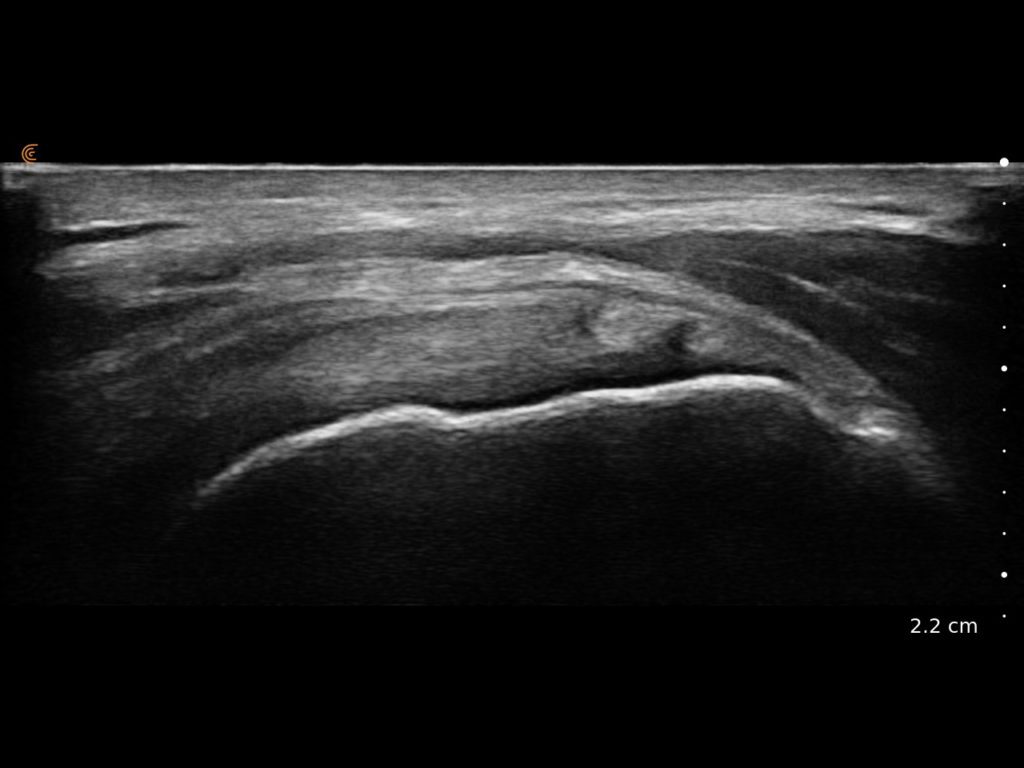

Elevate your sports medicine practice with high-definition dynamic imaging of muscles, joints, and tendons for accurate diagnostics and guided interventions on and off the field.